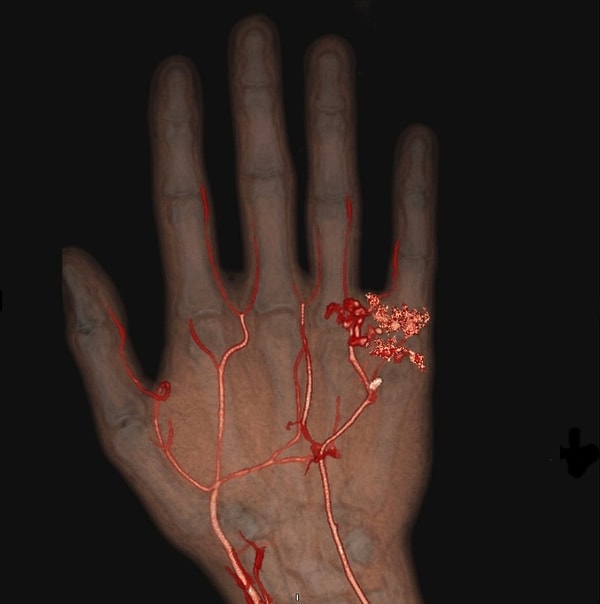

13. Damarların biçimsizleşmesini gösteren bir tomografi: